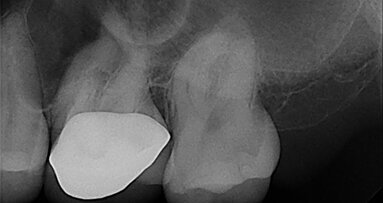

In this article, I report a case of a 33-year-old patient with irreversible pulpitis and symptomatic periapical periodontitis affecting tooth #26 (Fig. 1). ...